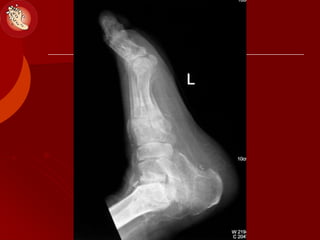

Natural History of Charcot Foot

 Stage of acute, destructive period

 Stage of coalescence: destruction, healing

 Stage of reconstruction: further repair and

remodelling of bone, restore stability

Charcot joints 1966 Springfield III

STAGES:

Natural History ofCharcot Foot  Stage of acute, destructive period  Stage of coalescence: destruction, healing  Stage of reconstruction: further repair and remodelling of bone, restore stability Charcot joints 1966 Springfield III STAGES: MIS